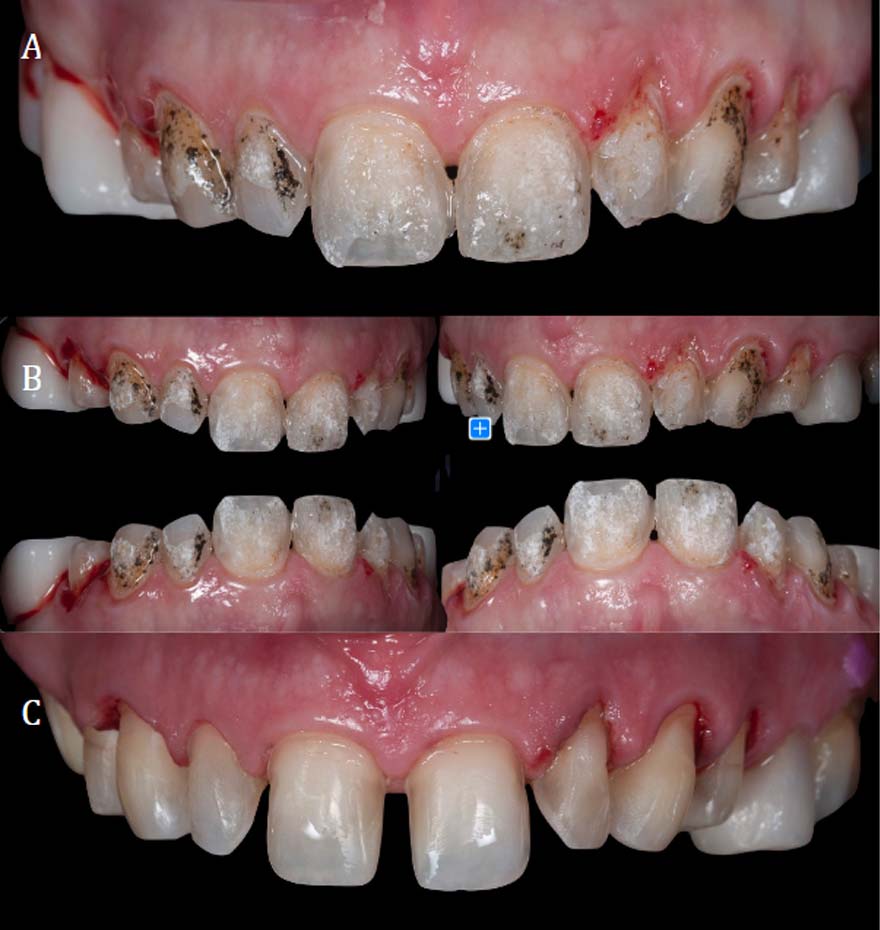

Clinical Case Presentation

A 55-year-old female patient was dissatisfied with the aesthetic outcome following the placement of eight porcelain veneers on her upper arch. Her primary concerns were the color and shape of the veneers. The veneers had been bonded at a thickness of 0.5 mm, with adhesive applied to the bucoccisal aspect. In this case, a decision was made to replace the restorations entirely, which meant that veneer integrity during removal was not a priority, in contrast to a scenario in which the existing veneer would be re-cemented, where preserving it intact would be essential.

The goal was to remove the indirect restorations using a minimally invasive approach, without damaging healthy enamel and while significantly reducing the time spent on the removal phase. Laser energy absorption in the cement manifests as a visible color change in the restoration due to the heating and energy uptake of the cement, which serves as a reliable clinical indicator during the procedure.